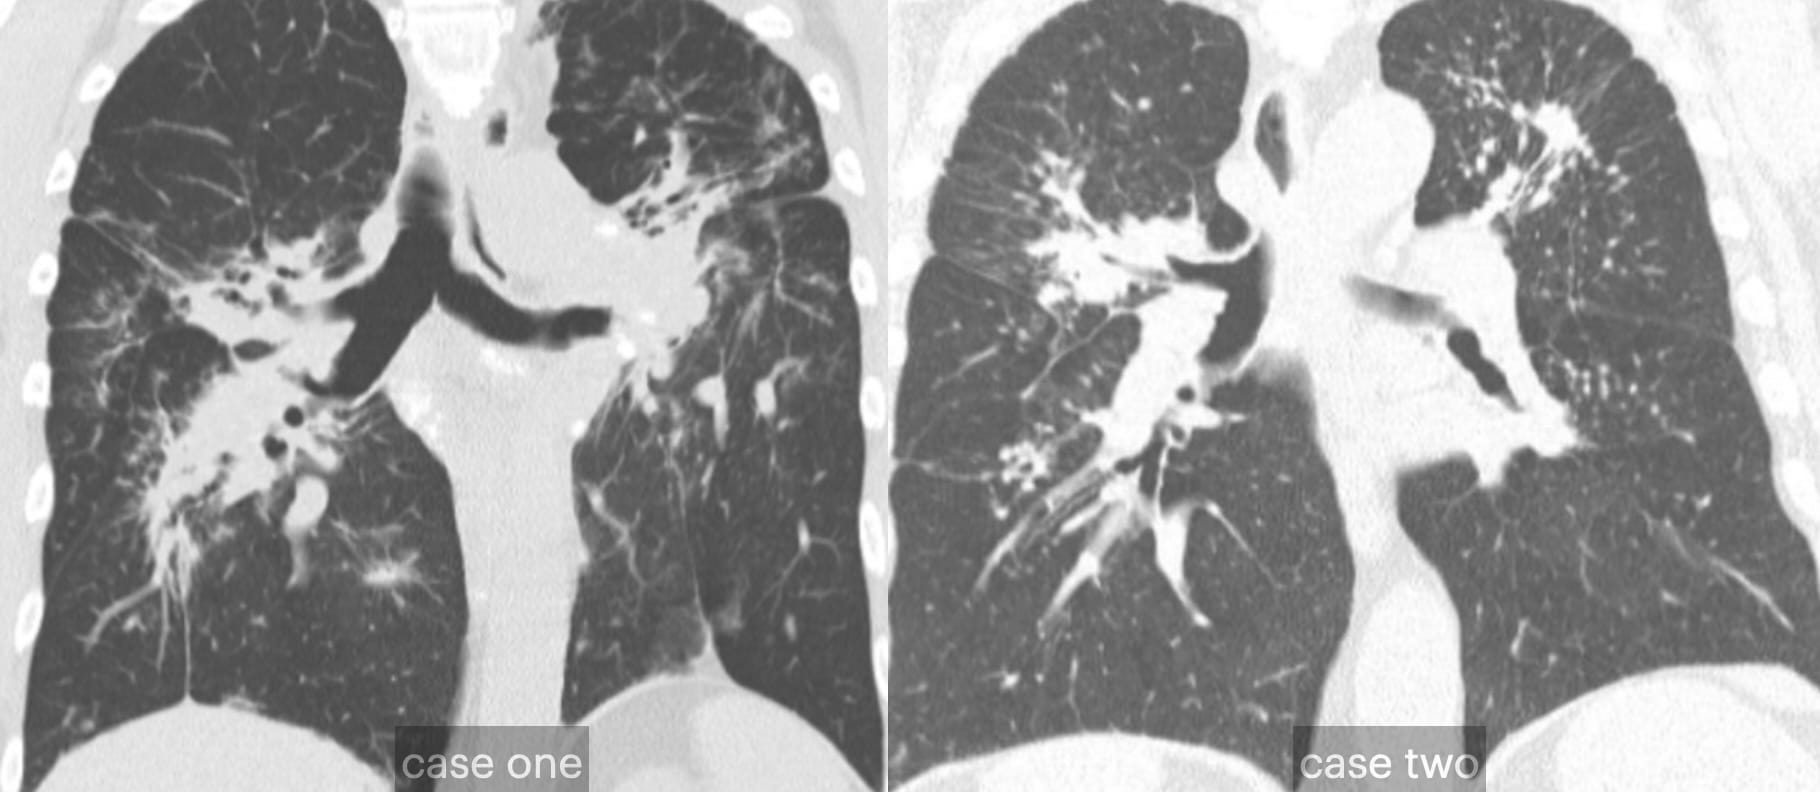

- Usual Interstitial Pneumonia

- Fibrotic Hypersensitivity Pneumonitis